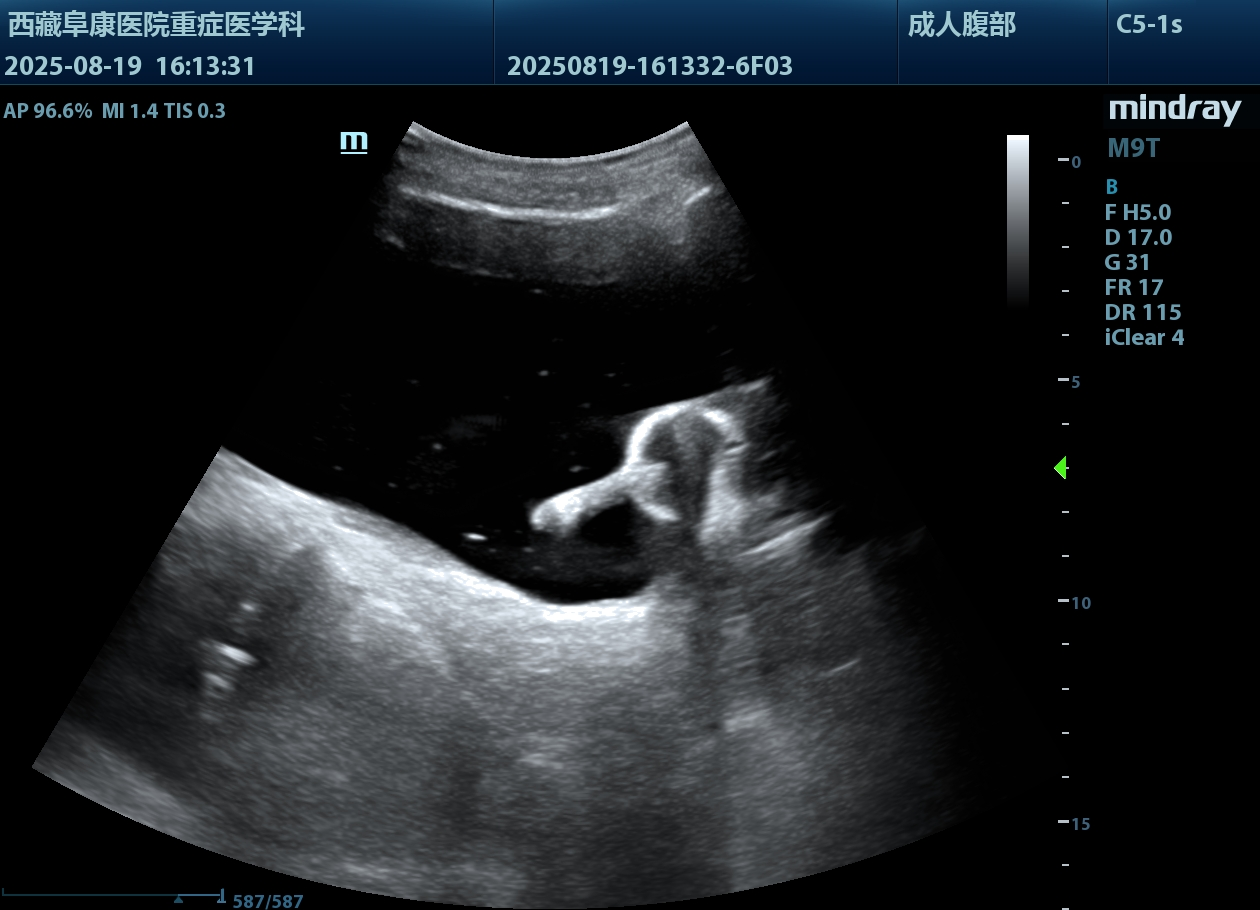

由于情況緊急,醫(yī)護(hù)人員沒有半分遲疑,除了導(dǎo)尿所需的物品,考慮到老人年紀(jì)大了,必須先確認(rèn)情況,半點(diǎn)馬虎不得,他們特意帶上B超機(jī),拎起出診箱,火速趕往老人家中。

推開門,只見老人蜷縮在藏式床上,身子微微發(fā)顫。醫(yī)護(hù)人員放輕腳步,俯身輕聲安撫:“大爺,我們先幫您看看情況,不難受的?!毕仁禽p柔查體,感知膨隆小腹下的膀胱充盈度;再用B超機(jī)細(xì)致探查,醫(yī)護(hù)人員邊操作邊低聲講解流程。慢慢地老人緊繃的身體放松下來,默許了檢查。可是提到導(dǎo)尿時,還是擺著手抗拒。醫(yī)護(hù)人員和家屬耐著性子反復(fù)勸說,許久后,他終于輕輕點(diǎn)了頭。